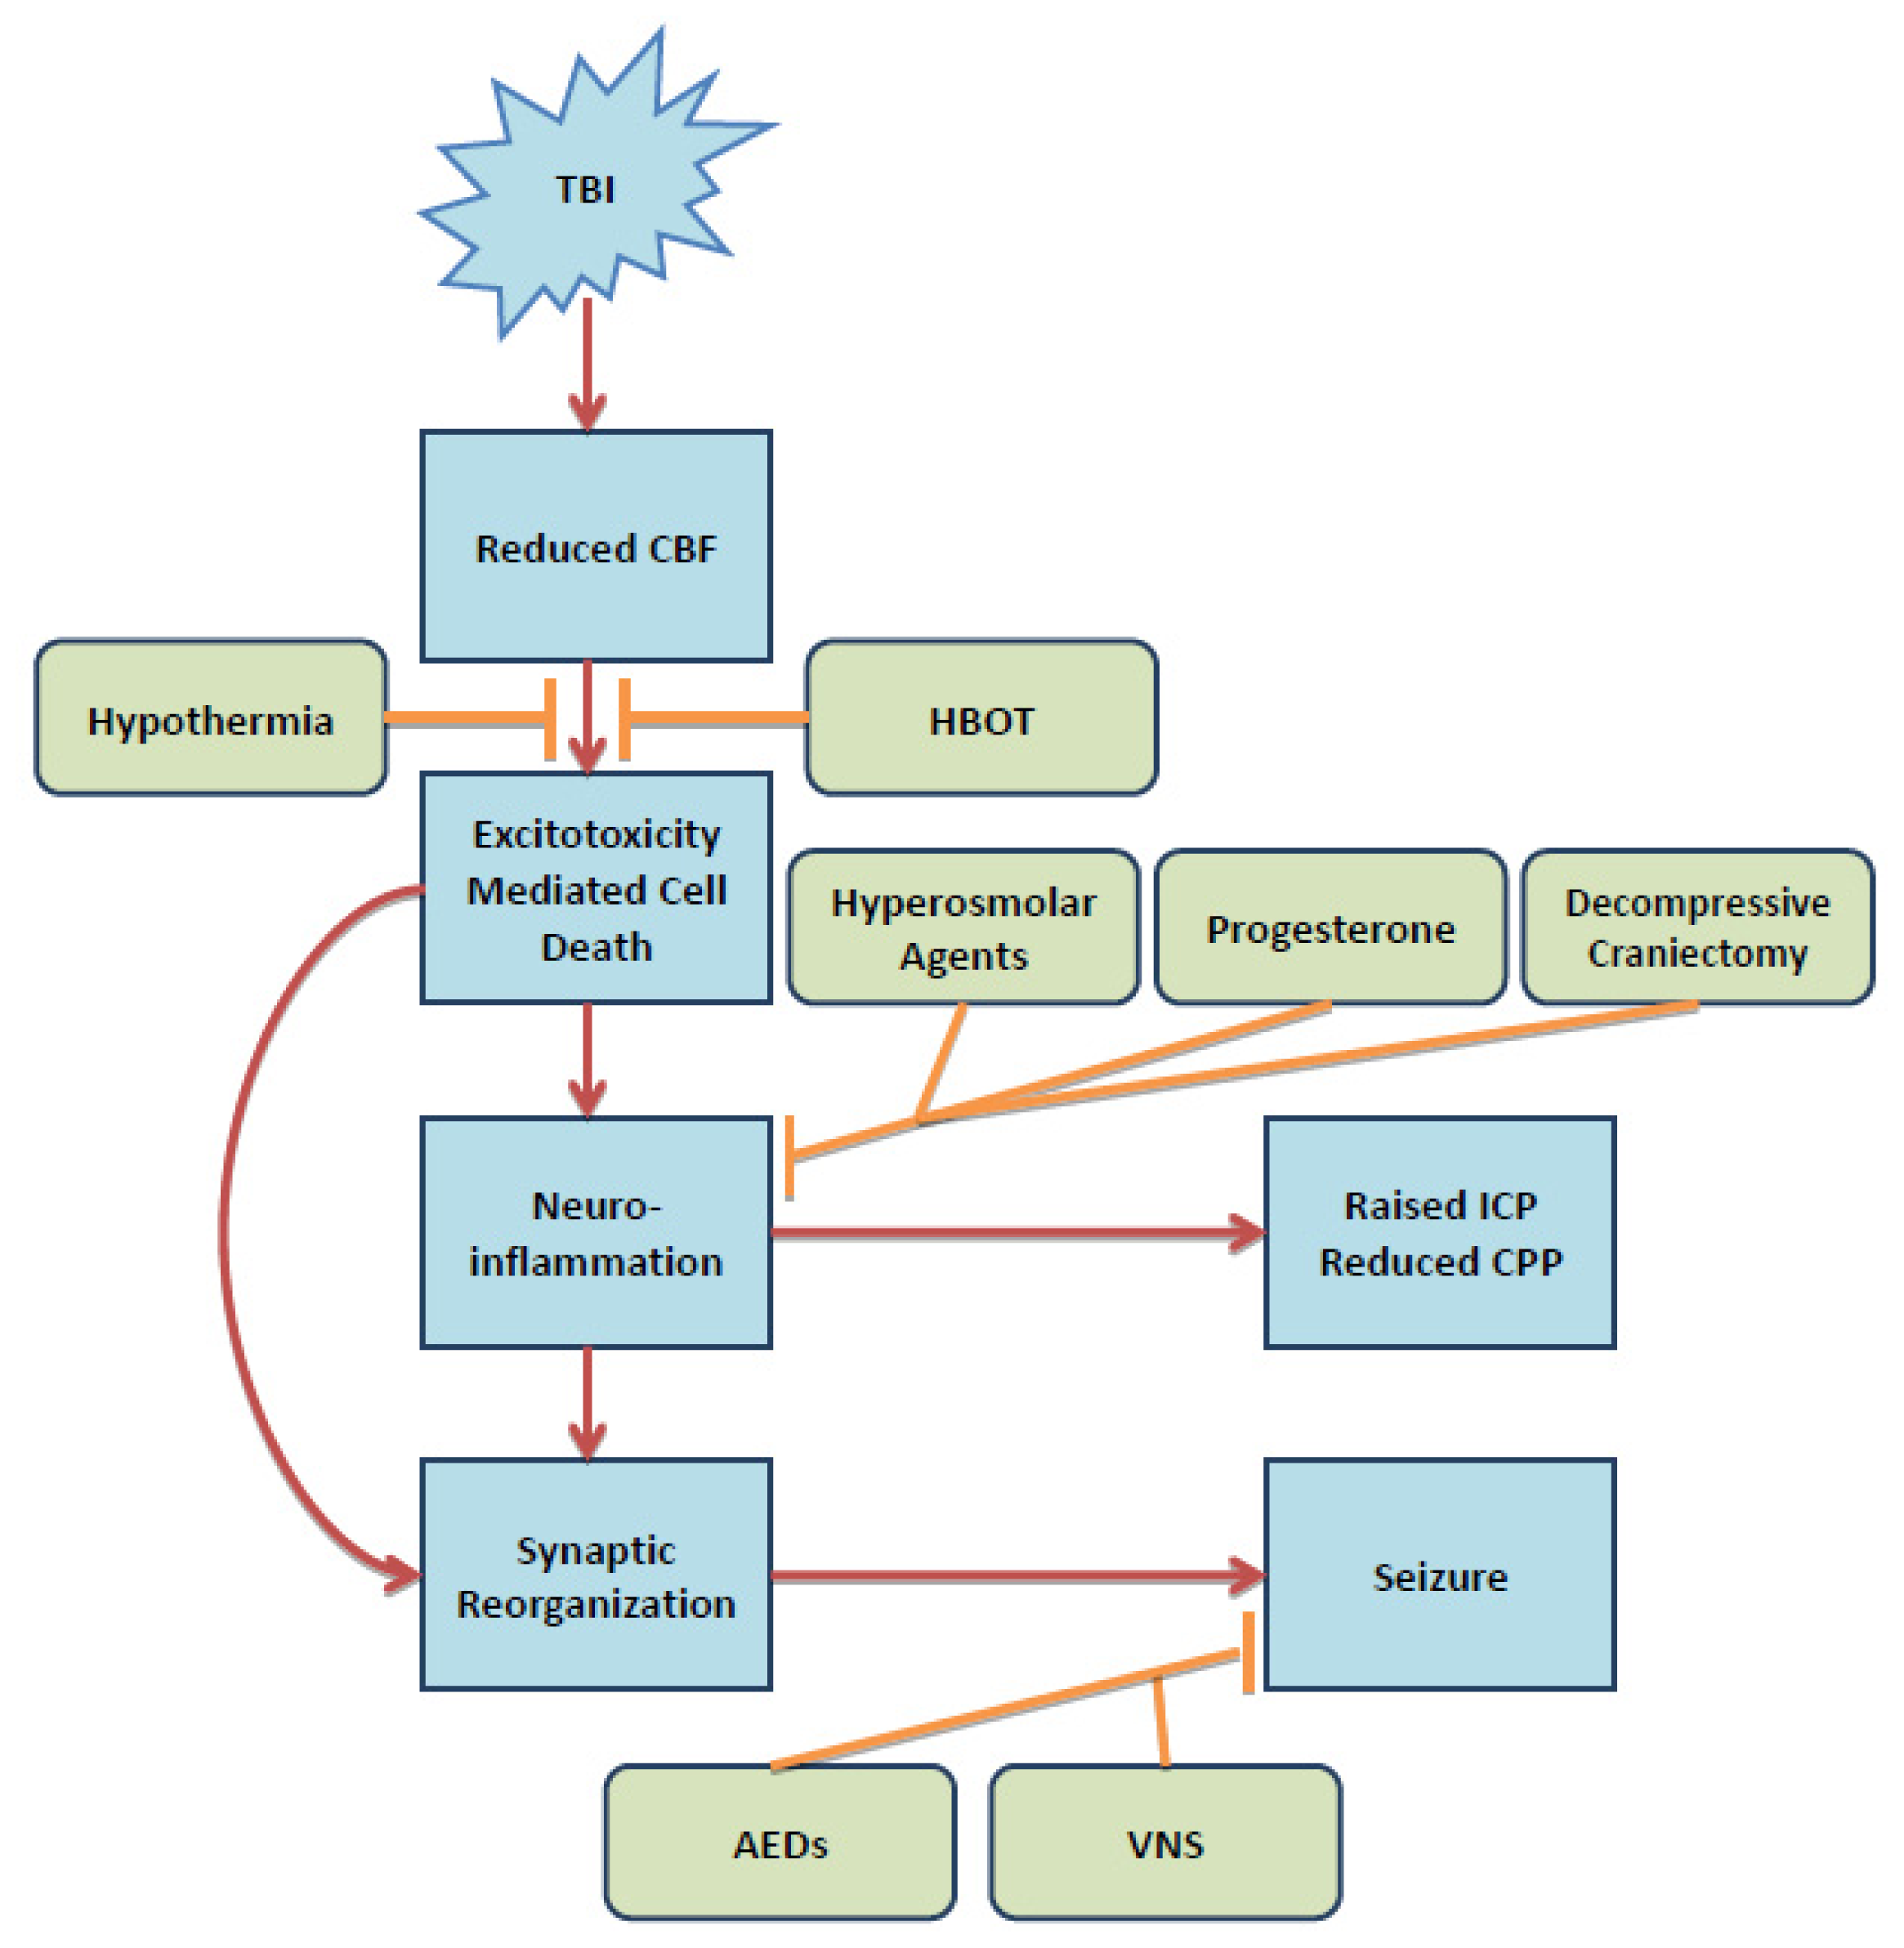

IJMS Free Full Text Traumatic Brain Injury Pathophysiology And

https://pub.mdpi-res.com/ijms/ijms-15-00309/article_deploy/html/images/ijms-15-00309f1.png?1403148131